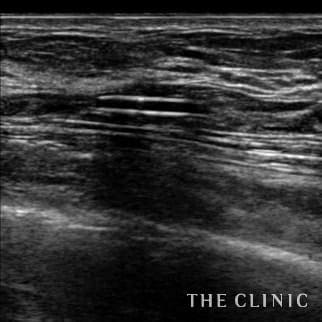

乳腺専用エコーを導入

術前後にエコー検査を行い、手術計画や結果についてを専門的に判断します。